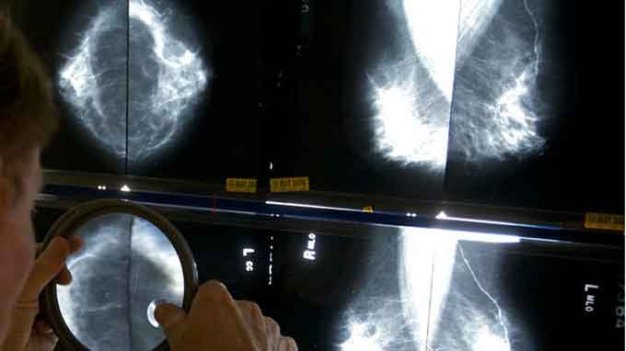

TTCT - Một nhóm chuyên gia từ viện nghiên cứu ung thư hàng đầu của Mỹ vừa đề xuất thay đổi một loạt định nghĩa về ung thư, loại bỏ một số định nghĩa về ung thư và loại bỏ từ này khỏi một số chẩn đoán để thay đổi cách chữa trị với căn bệnh này. Phóng to Các nhà khoa học đề xuất một số kết quả xét nghiệm chụp mammography không nên gọi là ung thư - Ảnh: A.P Những đề xuất này, từ một nhóm nghiên cứu của Viện Nghiên cứu ung thư Mỹ, được xuất bản trên số mới đây của tờ Journal của Hiệp hội Y tế Mỹ. Lạm dụng từ ung thư Theo các chuyên gia, một số tình trạng tiền ác tính, như tình trạng tiền ác tính có tên ductal carcinoma in situ (DCIS- ung thư ống dẫn sữa có giới hạn) mà rất nhiều bác sĩ đều cho rằng thực tế không phải là ung thư. Theo họ, căn bệnh này nên loại bỏ từ ung thư để bệnh nhân đỡ sợ hãi và đỡ tìm kiếm những biện pháp chữa không cần thiết và có thể gây hại như phẫu thuật cắt bỏ ngực. Nhóm chuyên gia này, theo New York Times, bao gồm những nhà khoa học hàng đầu về nghiên cứu ung thư, đồng thời đề xuất rằng rất nhiều thương tổn (lesion) phát hiện trong khi xét nghiệm ung thư vú, tuyến tiền liệt, tuyến giáp và các loại ung thư khác nên được phân loại là “thương tổn lan chậm có nguồn gốc biểu mô” (IDLE). “Chúng ta cần những định nghĩa của thế kỷ 21 cho ung thư thay vì những định nghĩa từ thế kỷ 19 mà chúng ta vẫn đang dùng” - Otis W. Brawley, bác sĩ trưởng của Hiệp hội Ung thư Mỹ, nói. Lý do cho những thay đổi này là sự lo ngại của bác sĩ, các nhà khoa học và bệnh nhân khi thấy hàng trăm ngàn bệnh nhân tiến hành những điều trị cắt bỏ và có hại cho những thương tổn tiền ác tính phát triển chậm - những thương tổn thường rất ít khi gây hại. Sự phát triển các kỹ thuật tầm soát ung thư trong những năm gần đây cho phép bác sĩ phát hiện những khối u ngẫu nhiên vô hại (incidentalomas). Tuy vậy, khi các khối u này được gọi là thương tổn lesion thì thường bác sĩ và bệnh nhân luôn muốn sinh thiết, chữa trị và cắt bỏ khối u này - điều thường gây nguy cơ tổn thương cơ thể và tâm lý với bệnh nhân. Vấn đề này được giới khoa học gọi là chẩn đoán quá (overdiagnosis) và kết quả là dẫn tới những chữa trị không cần thiết. Không chỉ là vấn đề tâm lý Nhiều nhà nghiên cứu đã cảnh báo nhiều về tình trạng chẩn đoán quá và chữa trị quá sau khi một nhóm nhà khoa học của chính quyền Mỹ đưa ra đề xuất nên chụp cắt lớp (CT) những người nghiện thuốc nặng mỗi năm một lần. Các thay đổi này dù có thể cứu 20.000 mạng sống mỗi năm nhưng một số bác sĩ cảnh báo hàm lượng phóng xạ tích lũy dần do chụp CT có thể dẫn tới những nguy cơ y tế nguy hiểm hơn. Các quan chức tại Viện Nghiên cứu ung thư Mỹ nói chẩn đoán quá là một nguy cơ y tế lớn và là vấn đề ưu tiên họ đang tập trung vào. Một cách để thay đổi, theo các bác sĩ, là nên gọi tên lại cho đúng các thương tổn được phát hiện trong quá trình chẩn đoán, tầm soát. “DCIS không phải là ung thư mà tại sao chúng ta gọi là ung thư” - bác sĩ Laura J. Esserman, trưởng nhóm nghiên cứu và là giáo sư tại ĐH California ở San Francisco, nói. Bác sĩ Larry Norton, giám đốc y tế của Trung tâm ung thư vú Evelyn H. Lauder, cho rằng vấn đề là bác sĩ đến giờ cũng chưa thể nói chắc chắn được những khối u nào sẽ không tiến triển và những u nào có thể giết chết bệnh nhân, vì vậy việc thay đổi cách gọi sẽ không giúp được nhiều. Dù vậy, bác sĩ Norton đồng ý rằng cần truyền đạt rõ hơn với bệnh nhân về tình trạng tiền ung thư và đã vào giai đoạn ung thư là thế nào. “Rất nhiều thuật ngữ có thể đánh lừa chúng ta, rõ ràng là cần phải giải thích rõ thêm - bác sĩ Norton nói - Nhưng không thể quay lại và đột nhiên thay đổi thuật ngữ của cả trăm năm nay như vậy”. Bác sĩ Esserman cho rằng việc đó là cần thiết. “Thay đổi ngôn ngữ chúng ta dùng để chẩn đoán các loại thương tổn lesion khác nhau là cần thiết để bệnh nhân hiểu họ không cần phải dùng các biện pháp chữa trị mạnh sau mỗi lần xét nghiệm. Vấn đề với dân chúng là mỗi khi nghe từ ung thư sẽ nghĩ mình có thể chết nếu không chữa trị. Chúng ta chỉ nên dành từ “ung thư” cho những thứ có thể gây hại thật sự” - bà nói. Tags: Ung thưLá thư bác sĩChẩn đoánCăn bệnhÁc tính